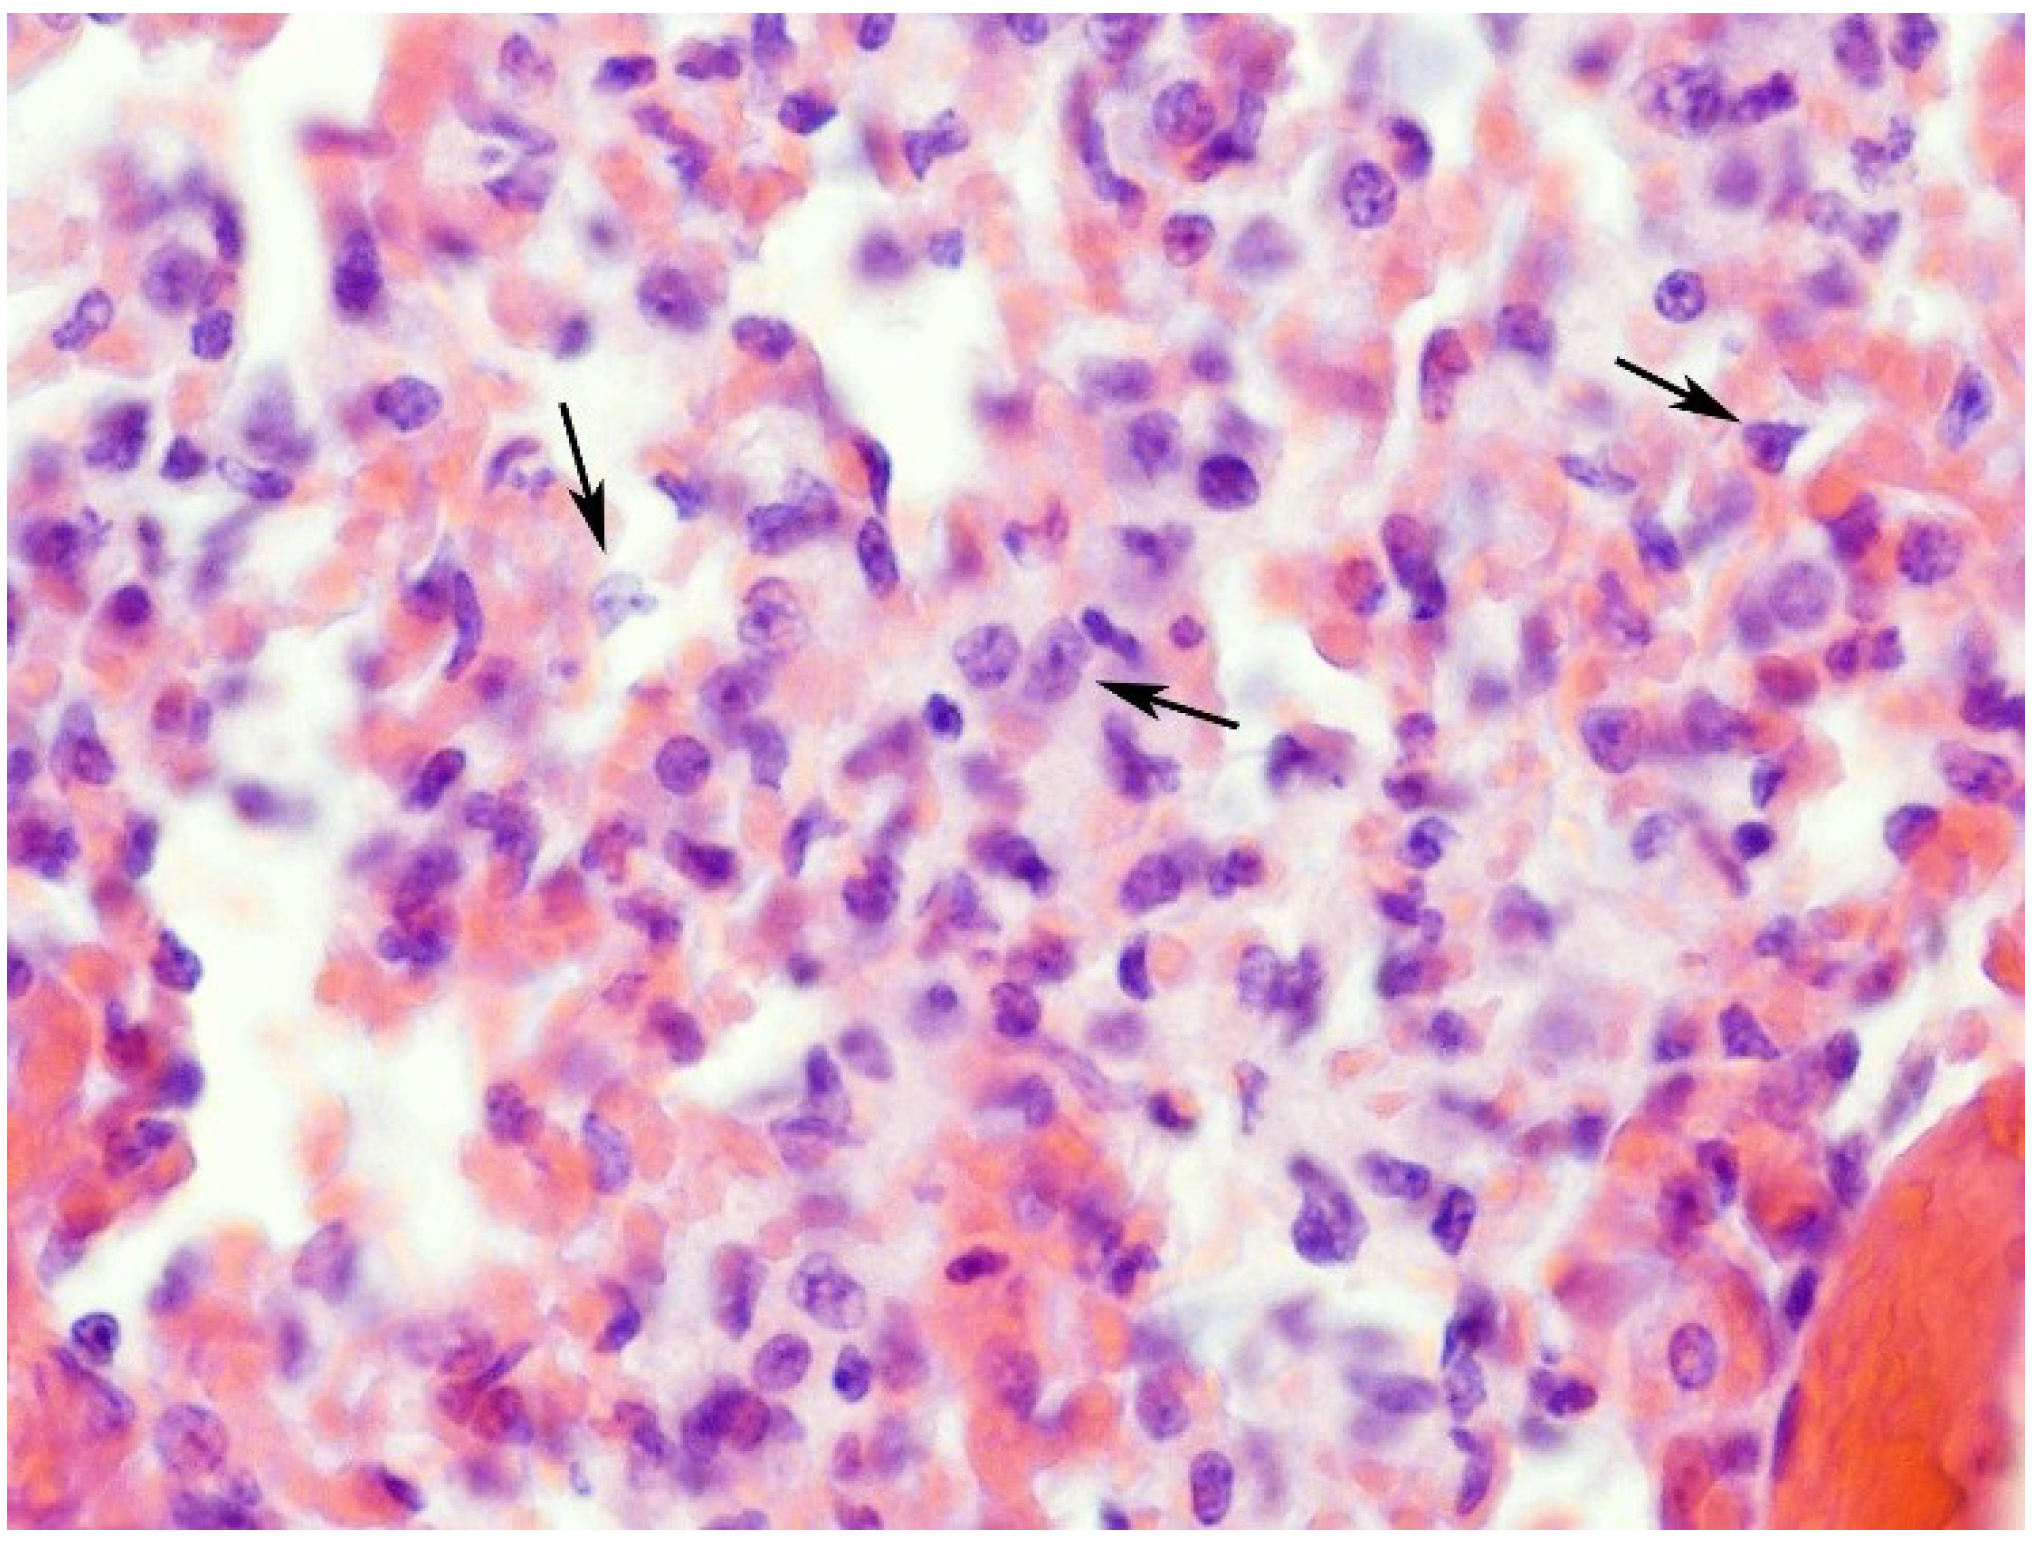

2.1. Effects on the Lung